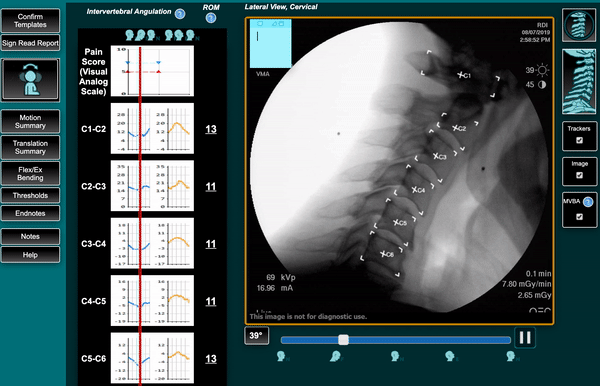

TruePath Imaging was founded on a simple idea: when patients and physicians see clearly, they make confident decisions. Our mission is to bring quantitative, motion-based spine diagnostics to the Chicago area, enabling clinicians to diagnose with precision and helping patients understand the root cause of their pain.

Our mission is to deliver clarity in cases where standard imaging leaves unanswered questions.